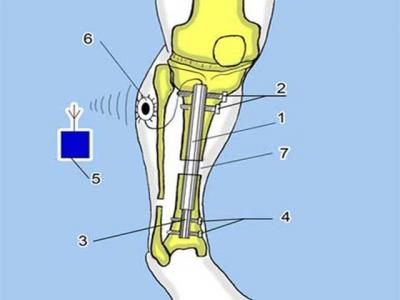

Trong năm 2013, một số tiến bộ Y học có thể sẽ được thị trường hóa và một số sẽ tiếp tục được thử nghiệm, đem lại nhiều hi vọng cho nhân loại. Dưới đây là những thành tựu Y học được mong đợi nhất năm nay. Chi tiết »